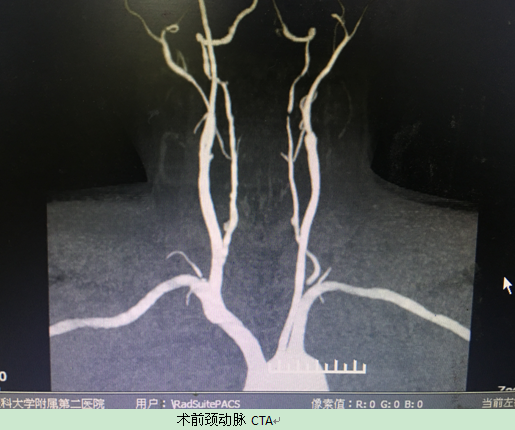

患者许某,61岁,以头晕、右侧肢体无力14天,发现左颈内动脉完全闭塞7天入院。患者入院前曾前往市内多家大型三甲医院就诊,均表示患者血管病变极重,手术风险极大,无法实施手术治疗,患者家属多方咨询后找到我院血管外科陈以宽教授。入院后,陈以宽教授,祁小桐博士,罗海龙博士积极安排患者完成相关检查,头颈部动脉血管成像(CTA)提示患者不仅左侧颈内动脉完全闭塞,还存在右颈内动脉重度狭窄(狭窄程度>90%)、双侧椎动脉重度狭窄(狭窄程度>95%)。尽管我院血管外科在处理包括颈动脉在内的周围血管疾病方面具有丰富经验,但多根颈部动脉同时出现严重病变的患者比较少见。